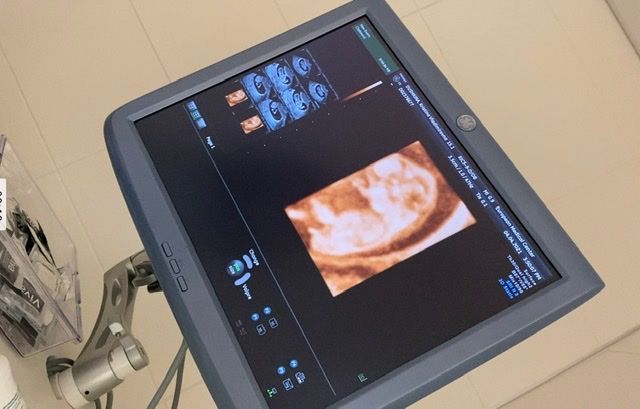

Дописала: пришел результат НИПТ-у нас будет мальчик 😍

Добрый день. Сегодня была на УЗИ, срок 10 недель и 4 дня. Врач не сказала пол, говорит боюсь ошибиться. Кто разбирается в половых бугорках? Сдала НИПТ через 2 недели узнаю пол))

Вика Москва, я сдавала в ЕМС. Они отправляют в Америку и там проводят анализ, поэтому минимум 2 недели((